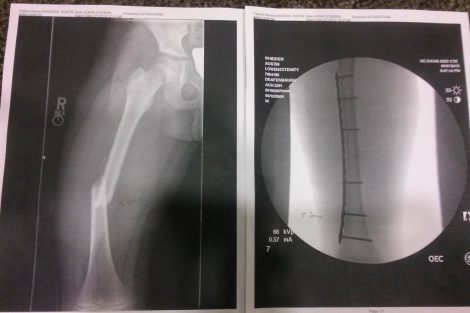

Austin was rushed to the UCD Med Center in Sacramento, where he underwent over 4 hours of surgery to repair the horrifying list of injuries…Broken right femur, Broken right ankle, Broken left tibia and fibula, multiple cuts and bruises to his arms and even his chin.

I spoke with Austin’s mother Ashley Whidden, who said that doctors repaired the injuries with metal plates and screws. The x-rays are horrifying.

Ashley said that he’ll have to have surgery again in 9 months to remove the plates and screws. Austin is resting comfortably, sleeping a lot, and even smiling at the pretty visitors.